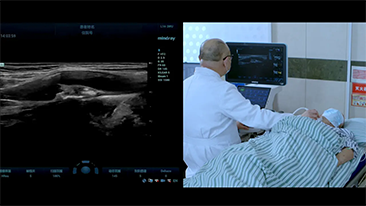

ImĂĄgenes generales

Las soluciones de imĂĄgenes generales de Resona de Mindray ayudan al personal clĂnico a realizar diagnĂłsticos y obtener resultados de tratamiento mĂĄs precisos y eficientes a travĂ©s de sondas para aplicaciones de subdivisiĂłn integrales y herramientas de aplicaciĂłn clĂnica eficientes.